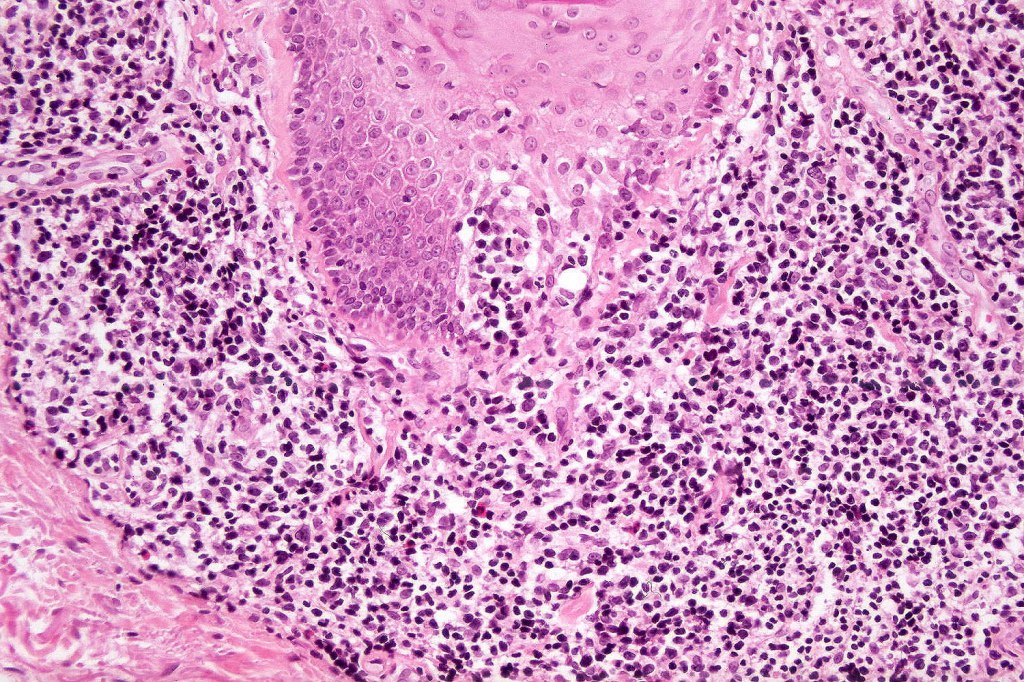

Histological features

•Follicular infiltration by atypical lymphocytes & Sézary cells

•Eosinophils sometimes conspicuous (eosinophilic folliculitis-like appearance)

•Granulomatous inflammation secondary to follicular destruction